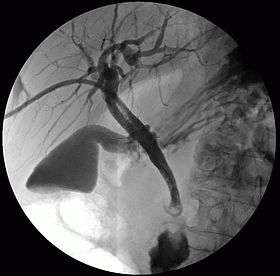

Cholangiography is the imaging of the bile duct (also known as the biliary tree) by x-rays. There are at least two kinds of cholangiography:

- percutaneous transhepatic cholangiography (PTC): Examination of liver and bile ducts by x-rays. This is accomplished by the insertion of a thin needle into the liver carrying a contrast medium to help to see blockage in liver and bile ducts.